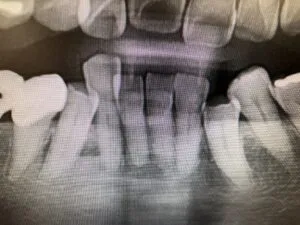

20年後のつい最近の手術した部分のレントゲンです。

ほとんど歯周病が進行していません。患者さんがずっとメンテナンスで通っていただいている成果だと思います。現在76歳で後期高齢者になられました。